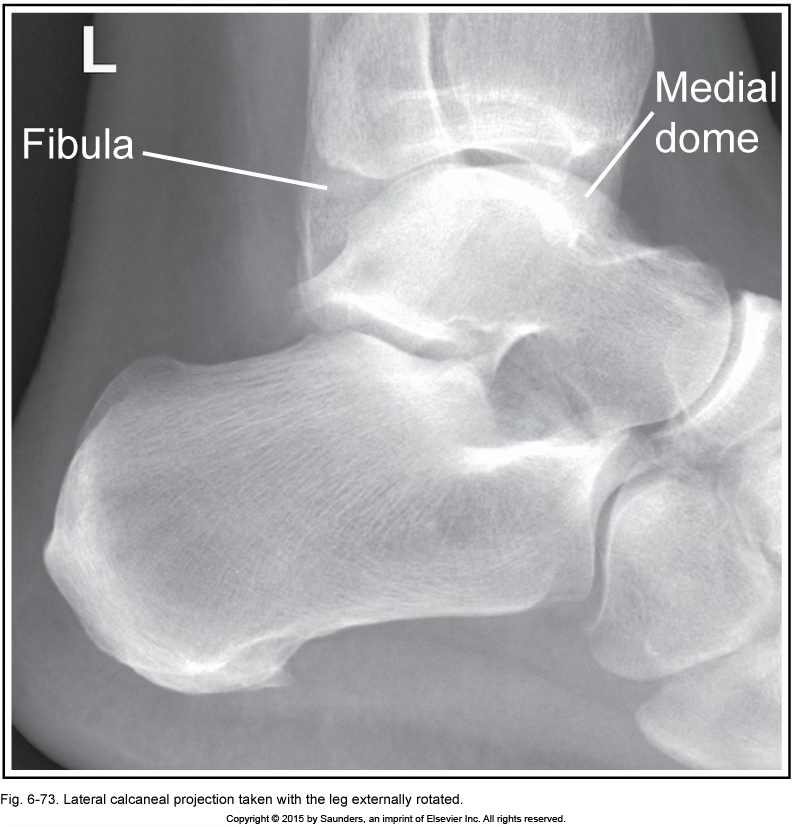

lateral calcaneus

leg externally rotated